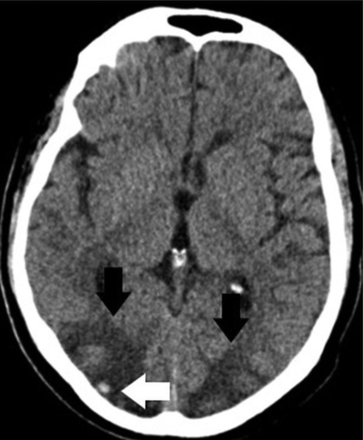

On March 25, she developed altered mental status, including lethargy and confusion, and was transferred to our hospital. In the emergency department, the patient was afebrile, with laboratory values notable for Cr = 1.65, blood urea nitrogen = 23, lactate = 2.3, and mild hyponatremia. Arterial blood gases were normal, and she denied cough, chest pain, and shortness of breath. The patient had variations in blood pressure, ranging from 115/72 to 178/83 mm Hg at admission. Chest CT demonstrated bilateral multifocal ground-glass opacities concerning for COVID-19 pneumonia due to its high prevalence in the region. Findings of a polymerase chain reaction test were positive for SARS-CoV-2 on March 27. Noncontrast head CT demonstrated edema in the bilateral parieto-occipital regions with associated mass effect and cortical sulcal effacement (Fig 3). MR imaging of the brain performed on March 27 revealed multiple areas of restricted diffusion with associated edema, most extensive in the posterior parieto-occipital lobes but also in the right frontal lobe, basal ganglia, and cerebellar hemispheres. The SWI sequence demonstrated extensive superimposed hemorrhages in the parieto-occipital region along with abnormal enhancement (Fig 4). Findings of concurrently performed MR angiography of the head and neck were unremarkable: Specifically, evaluation of the posterior circulation demonstrated a patent vertebrobasilar system. The patient remained afebrile with normal respiratory status, including oxygen saturation; after gradual improvement in her mental status, she was discharged.

Axial noncontrast CT images demonstrate vasogenic/cytotoxic edema in the parieto-occipital regions suggestive of PRES (arrows).